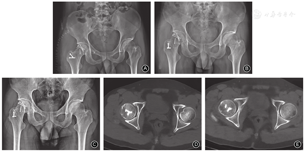

术中见股骨头前上方约2.5 cm×3.0 cm压缩,大小与术前CT测量结果一致;负重关节面软骨缺损,骨质塌陷。先应用骨刀凿除塌陷的骨软骨区,体积约3 cm×3 cm×1.5 cm;于股骨头内下头颈交接区取相同大小的骨软骨块,移植于压缩区域,修剪形状使股骨头关节面光滑;克氏针临时固定,再用直径3.0 mm的全螺纹无头钉埋头固定(常州华森医疗器械股份有限公司,中国)。取同侧3 cm×3 cm×2 cm髂骨外板修剪后植于股骨头内下供区,尽量保持髂骨外板和股骨头交界处光滑,克氏针临时固定后再用两枚3.0 mm全螺纹无头钉埋头固定(图4)。

固定完成后牵引患肢复位髋关节,并于各个方向活动髋关节,确认植入负重区的骨软骨块稳定,且股骨头与髋臼边缘无撞击等异常接触。"C"型臂X线机透视确认股骨头外形良好,关节间隙改善。缝合关节囊,以大量生理盐水冲洗,放置引流后逐层关闭切口。

术后第2天及3个月摄骨盆正位X线片示股骨头光滑、移植软骨块固定良好(图5A,B),平躺时可自主屈伸髋部。术后8个月患者根据自身情况逐步由部分负重增至完全负重后,髋关节无明显疼痛。术后2年骨盆正位X线片示股骨头光滑,无囊性变,无塌陷,无异位骨化,供区植骨块已骨性愈合,骨折线模糊;CT示股骨头光滑,关节间隙正常,骨质愈合良好(图5C~E)。患者负重行走时无疼痛,双下肢等长,患侧髋关节主动、被动活动良好,前屈、外展、内收、外旋等活动范围未见明显受限,与健侧髋关节活动相当。Thompson-Epstein标准评价等级为优,髋关节Harris评分100分,Merle d'Aubigne功能评分17分。